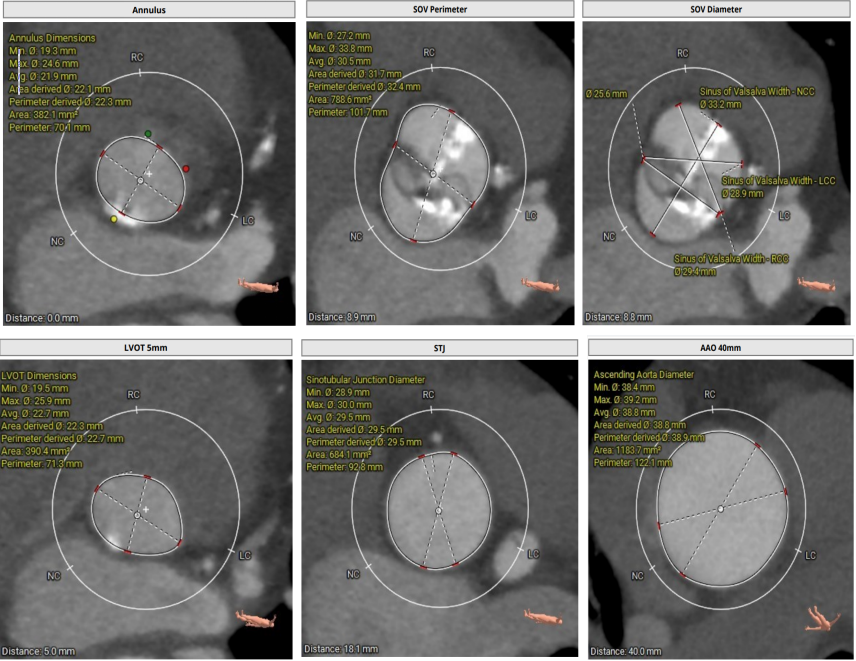

术前CT评估

Type1型二叶式主动脉瓣,瓣叶增厚,L-R钙化融合嵴,左冠瓣及无冠瓣对合缘局部钙化,并可见无冠窦向左室流出道延伸长钙化;左室流出道呈微敞口型;

左冠开口偏低,右冠脉开口高度尚可,左右冠瓣叶冗长,切线位测量左右冠瓣叶长度>瓣叶附着缘到冠脉开口距离;左主干及回旋支局部钙化;

窦管交界内径适中,瓦氏窦内径适中,升主动脉内径稍扩张;

瓣环水平夹角为51°,主动脉弓角度尚可,弓距尚可;

主动脉根部及外周入路血管

主动脉根部